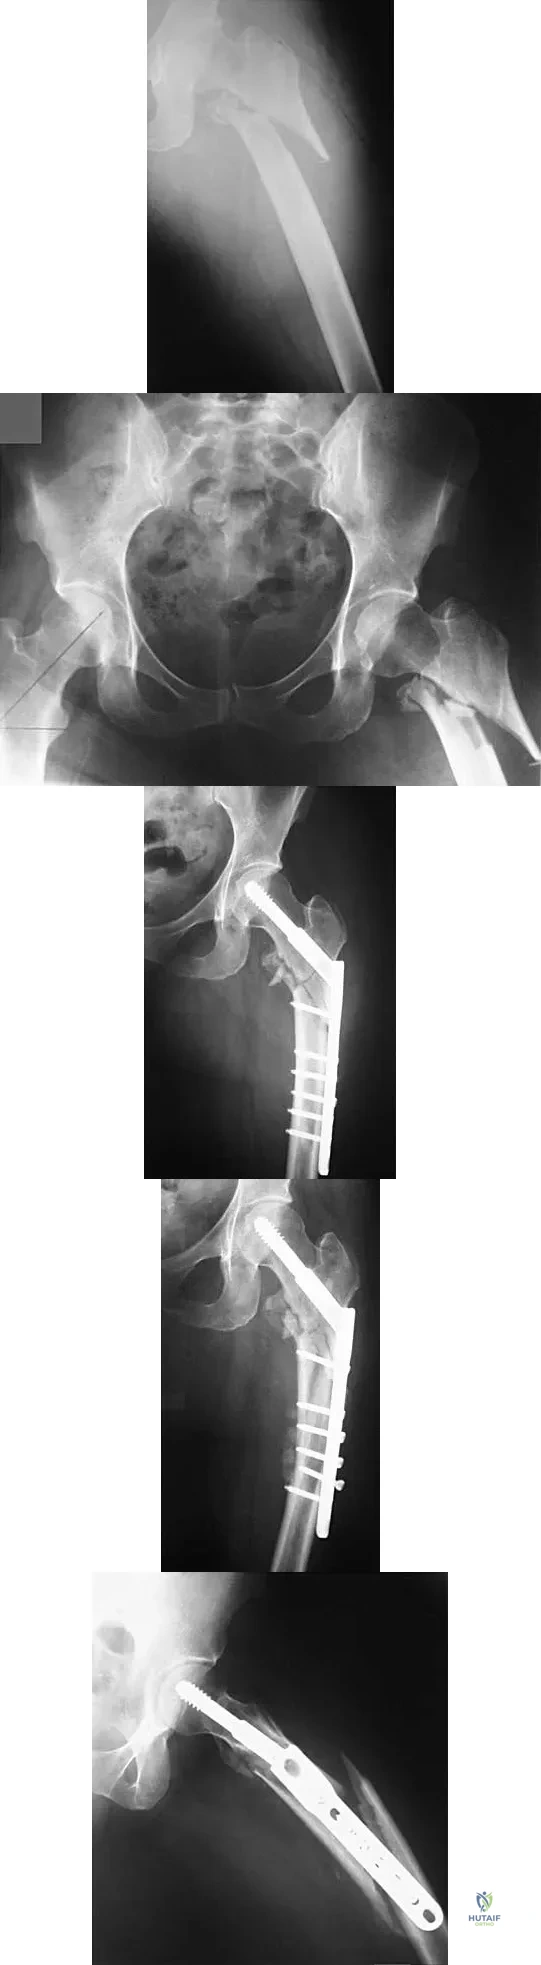

Question 76High Yield

Figures 7a and 7b show the radiographs of a 51-year-old woman who injured her left leg after falling off a stepladder. Surgical reconstruction is performed with a compression screw and side plate; the postoperative radiograph is shown in Figure 7c. Following gradual progression of weight bearing, she reports that she slipped again and placed full weight on the extremity. She now notes a new onset of increased pain in her left thigh and hip region. Follow-up radiographs are shown in Figures 7d and 7e. Reconstruction should consist of

Explanation